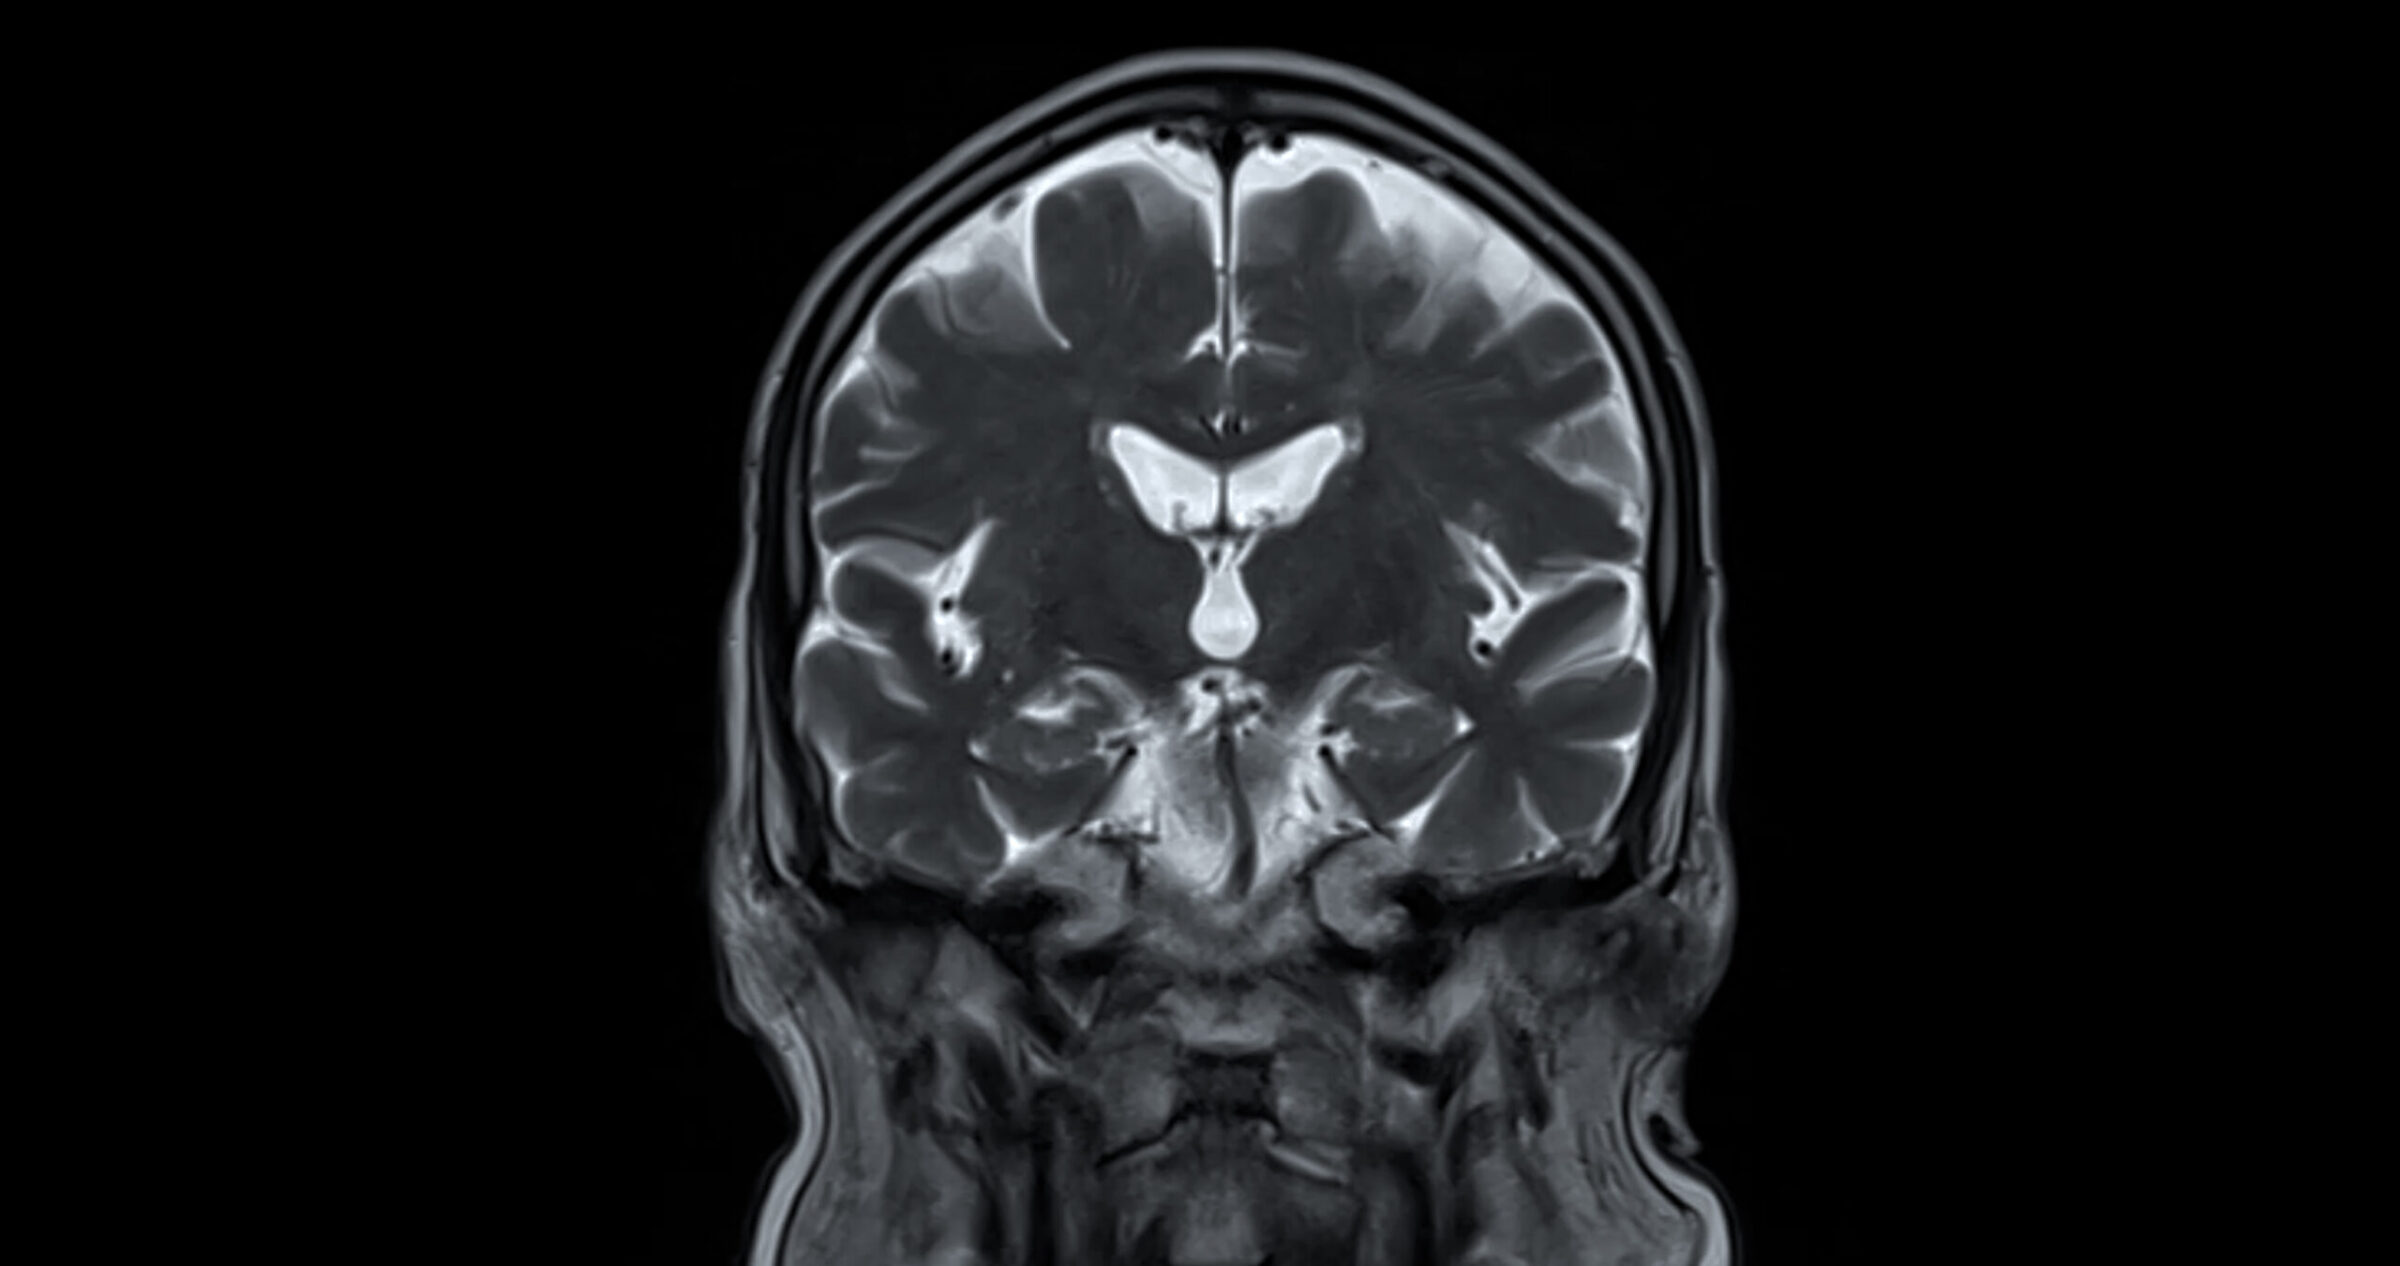

Every case of vascular dementia involves some kind of changes to the blood vessels in the brain. When the brains of people with vascular dementia are studied via MRI, clinicians can sometimes see the traces left by strokes (including mini-strokes) that the person may have had. Often, the small blood vessels of the brain are damaged and the white matter has become diseased.